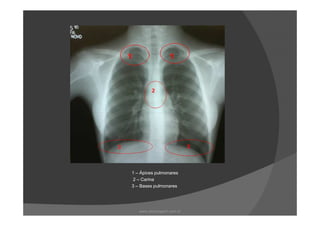

As regiões radiograficamente importantes do

pulmão são:

Ápice

Carina

Base

DiafragmaDiafragma

Tórax PA

1 – Ápices pulmonares

www.playmagem.com.br

2 - Carina

2 – Carina

3 – Bases pulmonares

1 – Ápicespulmonares 2 – Carina 3 – Bases pulmonares www.playmagem.com.br